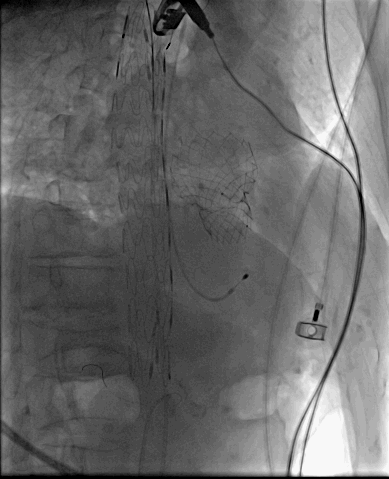

全麻气管插管,通过右颈内静脉留置临时起搏器于右室,以右侧股动脉作为主入路,经皮穿刺,预置2把Proglide缝合器。主动脉根部造影可见主动脉瓣钙化影,主动脉瓣中-重度返流。

TAVR术前主动脉根部造影

再行降主动脉造影见降主动脉穿透性溃疡。

TEVAR术前降主动脉造影